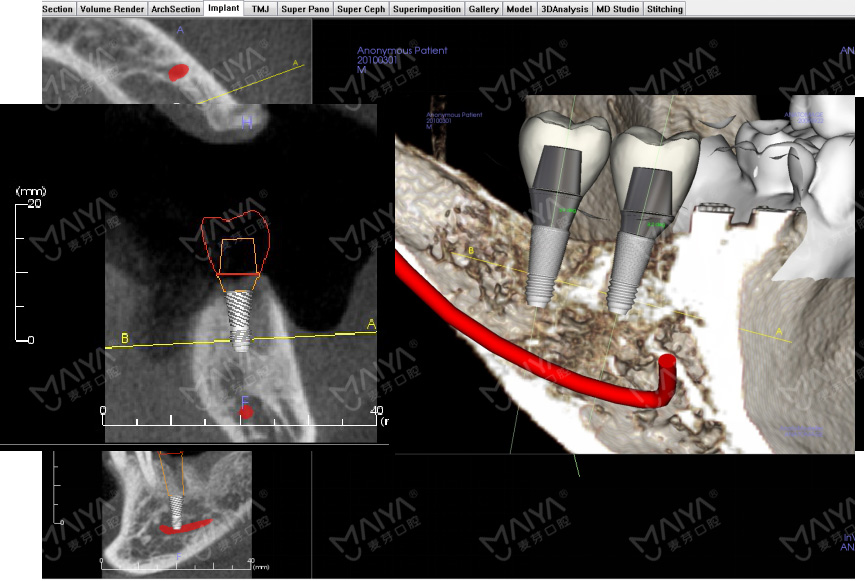

本次研讨会将聚焦临床医师关注的核心技术问题,展开深入的交流与探讨,从骨缺损分类、无牙颌生理解剖、CBCT的影像学分析、颌位关系变化、诊断排牙、种植体的数量、位置、型号及材料选择标准、咬合设计等细分环节,重点剖析,逐项解疑,更将针对无牙颌种植修复的流程设计与风险把控进行案例分享。